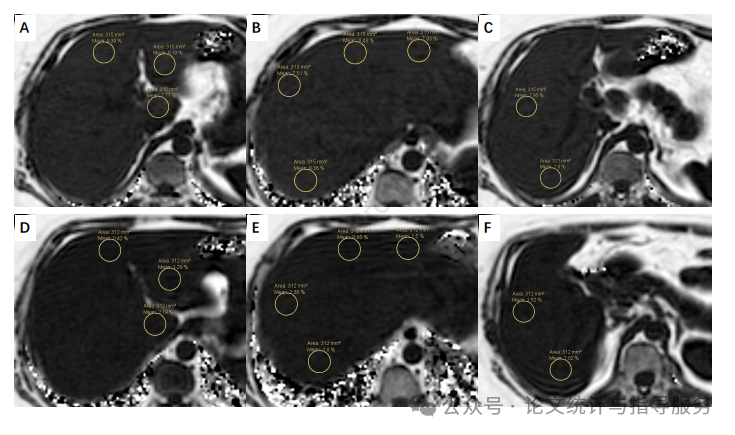

为期12周的槲皮素干预使患者的平均肝内脂质含量从11.5%适度降低至9.6%(P=0.013,调整后的P值为0.028,ANOVA的FDR调整P值为0.026,ANCOVA的FDR调整P值为0.028,表明肝内脂质含量百分比降低了17.4%,而安慰剂干预后仅降低了0.9%。在多重线性回归的最终模型中,常数为1.509,体重变化、能量摄入变化和干预的系数分别为0.563、0.006和-1.421(P值分别为<0.001、=0.001和0.010),且r²为0.416。这些结果表明,12周的干预降低了NAFLD患者的肝内脂质含量。

【一位受试者先后服用安慰剂胶囊和槲皮素胶囊后,通过MRI-PDFF测量的肝内脂质含量图像】